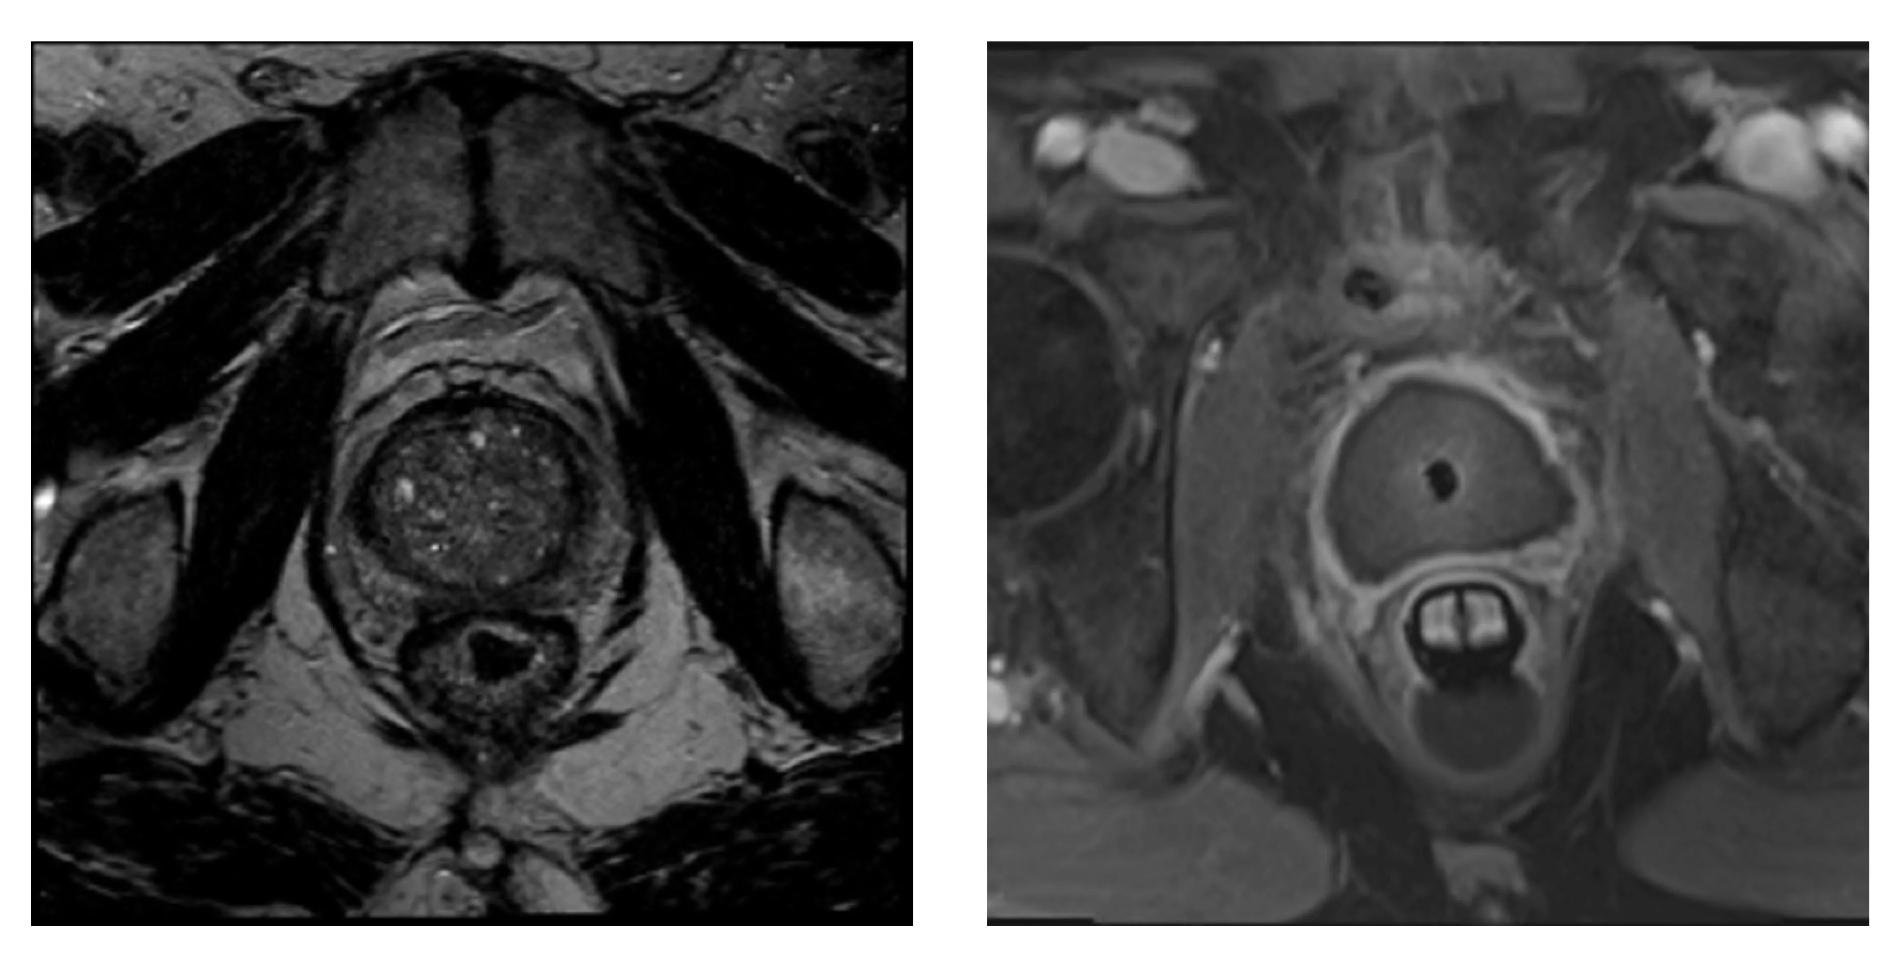

The UA is built with 10 tiny transducer elements. Each one can send ultrasound energy into the prostate, and the doctor can turn them on and off to match the prostate’s size and shape. While they send energy into the prostate, the UA also keeps the urethra cool to shield it from the heat. In the picture below, you’ll see that only 9 out of the 10 elements were enough to reach the target tissue.

The doctor views the prostate from three angles: axial, sagittal, and coronal. With these three perspectives, the doctor outlines the treatment borders that correspond to each ultrasound element.